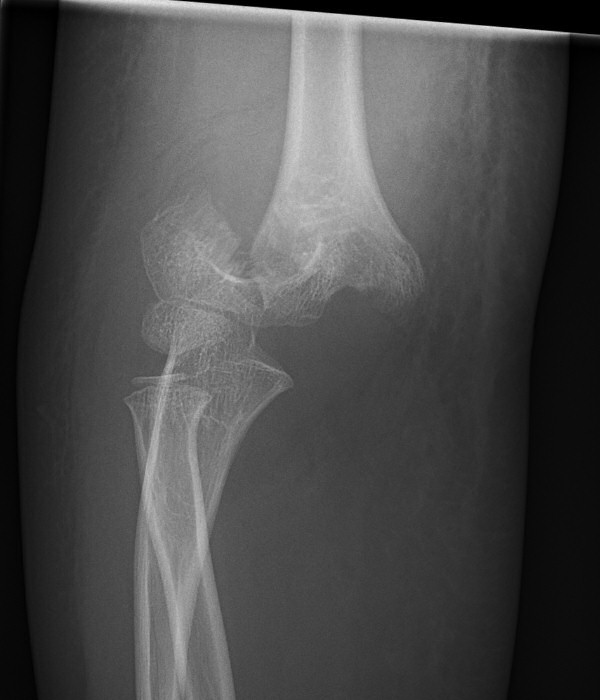

Suprakondylar humerusfraktur, Gartland 3, före och efter operation med stiftning